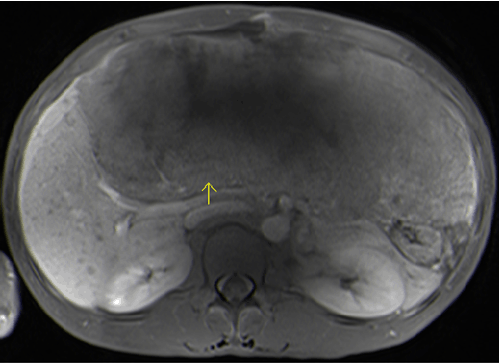

White blood cell count was 11.6 k/UL, hemoglobin 11.7 g/dL, hematocrit 34.4%, platelet count 306 k/UL. Total protein 7.6 g/dL, albumin 4.1 g/dL, total bilirubin 1.2 mg/dL, direct bilirubin 0.1 mg/dL, ALT 77 units/L, AST 337 units/L, alkaline phosphatase 320 units/L, CEA 25.7 µg/mL, alpha fetoprotein level 4 ng/mL. Computed tomography scan of abdomen reported "Bilateral pulmonary nodules suspicious for metastatic disease, enlarged right pericardial lymph node. Large heterogeneous mass in the upper abdomen, which may be arising from the liver, although a lytic lesion could not be excluded. Additional focal lesion in the right lobe of the liver is identified. Malignancy is suspected. Extensive ascites. "MRI scan of the abdomen with Eovist was obtained (Figure 1) and showed 24x23x12 cm heterogeneously enhancing mass replacing the left lobe of the liver suspected for hepatocellular carcinoma. Numerous hepatic and pulmonary metastases are present.

Figure 1: Magentic resonance imaging scan of the abdomen with Eovist. MRI showing the liver mass measuring 24x23x12 cm, arrow pointing to the posterior surface of the mass. Eovist is a contrast agent specifically used to evaluate liver lesions found on other imaging studies.